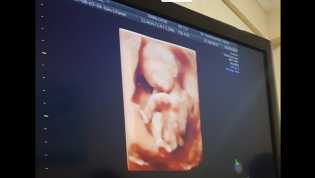

Penemuan Janin Bayi dalam Jok Motor di Riau, Ini Tersangkanya